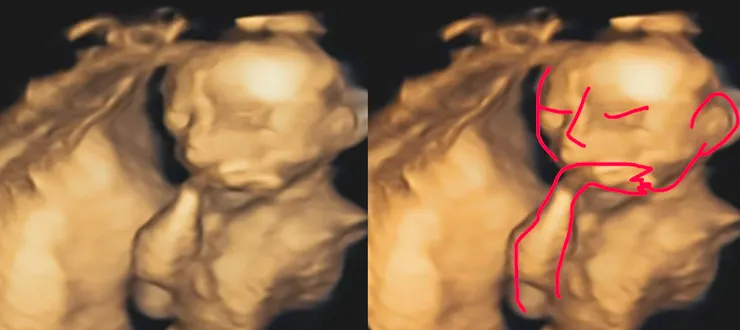

郭醫師說我的寶寶是沉思者!

另外就是情緒價值給好給滿的超音波時間!每次產檢都會先照超音波,醫師都會邊照邊跟寶寶說話,「好好笑喔,很會擺姿勢以後當model喔!」「怎麼不動了呢?快點把手手移開給阿姨看看臉!」然後笑得很開心,我也會郭醫師情緒感染到,聽到醫師跟寶寶講話都會笑出來,醫生形容寶寶的表情跟動作也都很具體,好像在面對真的人,讓我常常好想哭,覺得我肚子裡真的有一個寶寶(本來就有??),這種感覺很難形容,我知道婦產科醫師看過的孕婦跟寶寶非常多,但郭醫師卻還是保有熱情,認真對待我的寶寶。

可能我太鄉巴佬了,照高層次那天真的滿滿amazing,科技好發達喔!以為照照手指頭、照照器官,想不到是超級精密的照,還可以看到血管、心臟跳動等等,而且是超詳細的照器官!小蛇寶寶算很配合,全程很high動來動去,不過是有點動太快,還看到他搓腳、打哈欠,真的覺得⋯⋯好可愛喔!我已經開始變笨蛋媽媽了嗎?全部大概1小時10分鐘搞定,真是乖孩子。